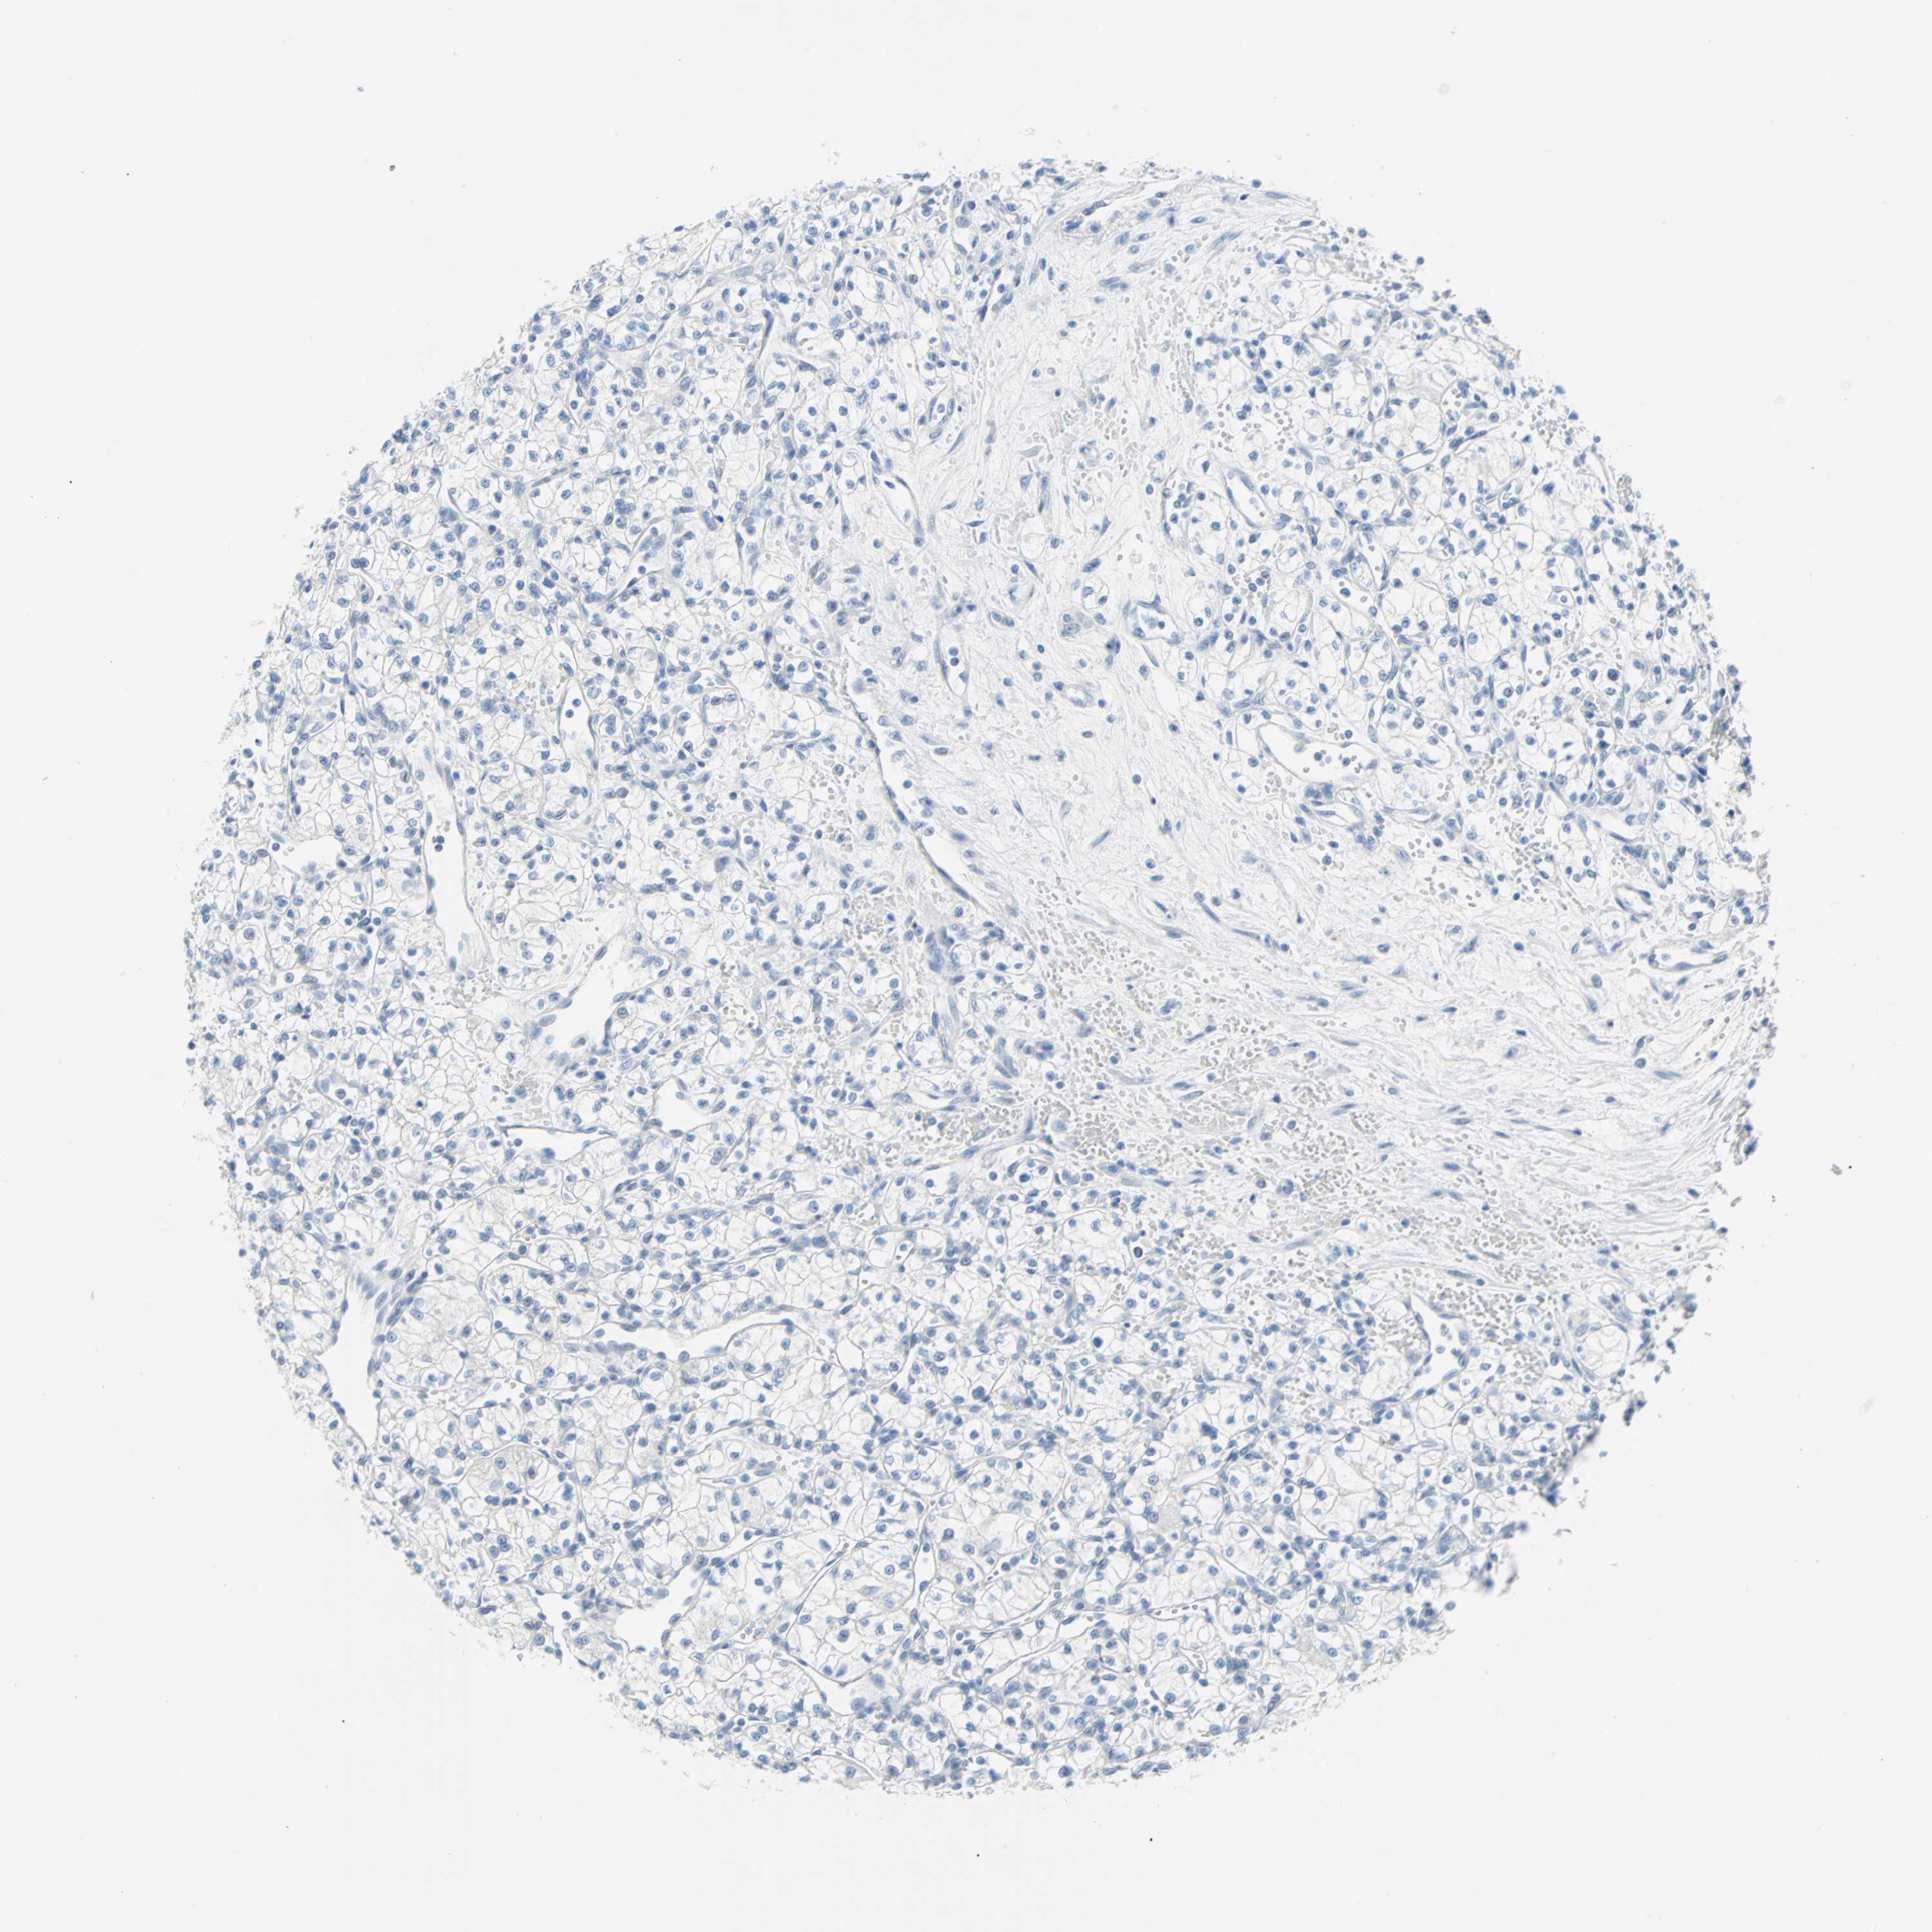

Renal cancer

Human cancer

Kidney chromophobe

Kidney renal clear cell carcinoma

Kidney renal papillary cell carcinoma